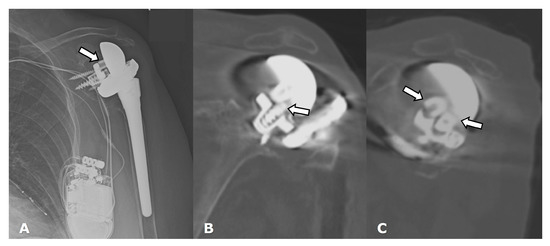

4.2.1. Loosening and Hardware Dissociation

5.2. Reverse Arthroplasty

Reverse Total Shoulder Arthroplasty (RTSA)